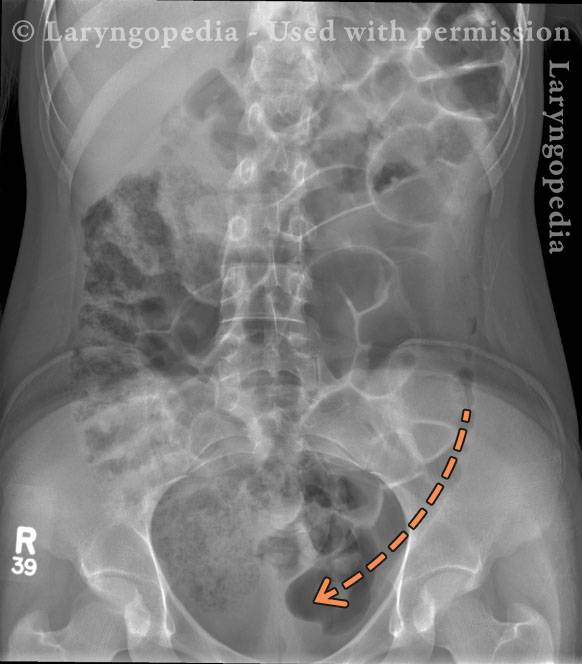

Intraluminal gas (2 of 2)

This image demonstrates distal transit of intraluminal gas. The curved arrow shows the direction of air progressing through the colon toward the rectum, explaining the patient’s continued ability to pass flatus and arguing against a mechanical obstruction.